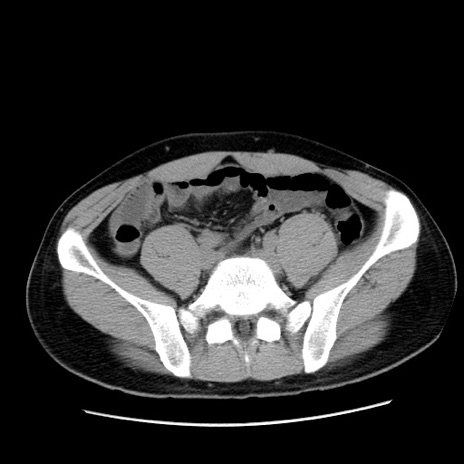

症例36(横断像)

【症例】20歳代 男性

【主訴】心窩部痛

【現病歴】今朝より上腹部痛あり。一旦軽快していたが再度出現したため救急要請。昨日夕に白身の魚を含む刺身を食べた。

【身体所見】BP 136/89mmHg、HR 74/min、BT 37.0℃、腹部:膨満、軟、心窩部に圧痛あり。反跳痛なし、筋性防御なし、腸雑音やや亢進あり。

【データ】WBC 17700、CRP 0.48